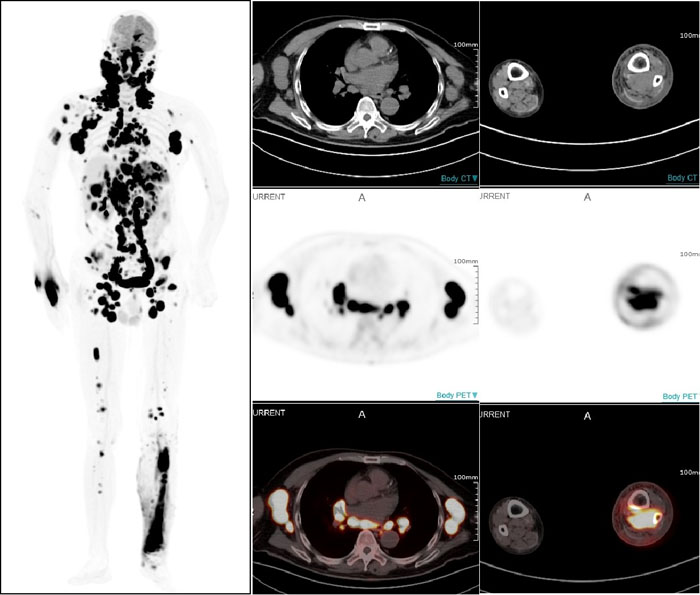

PET/CT显示:全身多部位淋巴结和多个结外器官及不易发现的左小腿后方肌肉组织淋巴瘤受累病灶

一名67岁男性患者因近期无明显诱因出现左颈部淋巴结肿大而就医,淋巴结切检病理诊断为非霍奇金弥漫大B细胞淋巴瘤。借助全景动态Total-body PET/CT扫描,不仅确认了此前的诊断,还发现肿瘤已广泛累及全身多处淋巴结及乳腺、胸膜、肝脏、脾脏、胃等多个结外器官。更令人称奇的是,连平时难以察觉的右小腿深部肌肉组织病变也被准确捕捉。这一全面而精确的影像信息,有效提升了治疗的针对性,为医生制定个性化治疗方案奠定了坚实基础。

设备全身动态采集的性能,清晰展现出药物在体内的流动、扩散及被组织器官摄取并代谢的全过程,帮助医务人员观察药代动力学改变,可以预见,将为肿瘤诊疗、新药研究、细胞追踪等领域带来更多革命性突破。